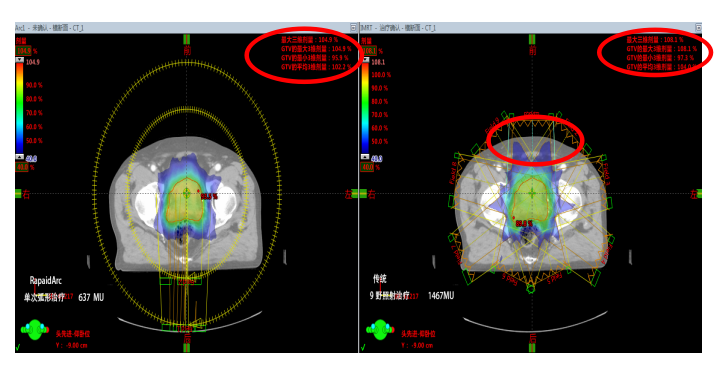

1.出色的劑量分布:傳統9野照射治療需出1467MU而RapidArc只需637MU。在確保達到優(yōu)化劑量分布的前提下,使得機器跳數達到最??;RapidArc相比于傳統動態(tài)調強具有更均勻的劑量跌落和更低的最大劑量的優(yōu)勢。

2.出色的放療質量:更少的漏射線、散射線,對患者正常組織和危及器官提供更好的保護,靶區(qū)適形度更好、劑量更飽滿。